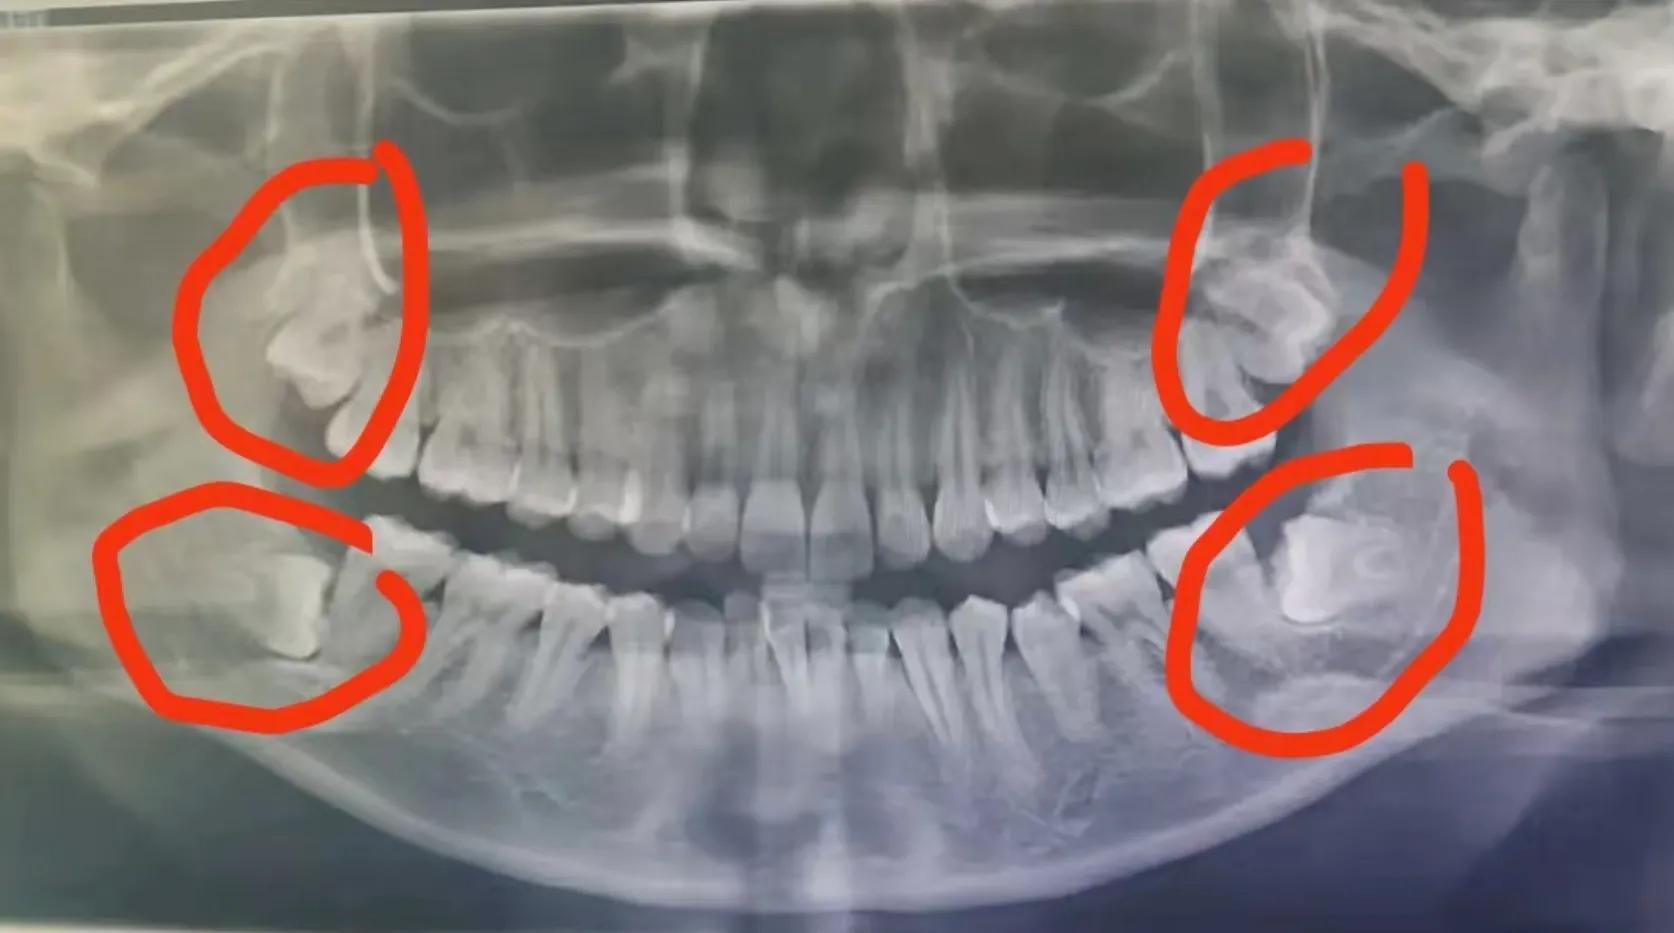

“当然,智齿到底拔还是不拔我们需要专业的牙医经过仔细的检查研判后才能给出专业的治疗意见,有了问题直接去找医生就对啦,而不是自己胡思乱想下结论自己吓自己。因为专业的牙医也需要第三张图的“慧眼”—— 全景X线片 来发现阻生的智齿呈现出来的各种“睡姿”(图中红圈处)。”

图3. 全景X线片检查阻生齿的各种姿态(图片来自网络)